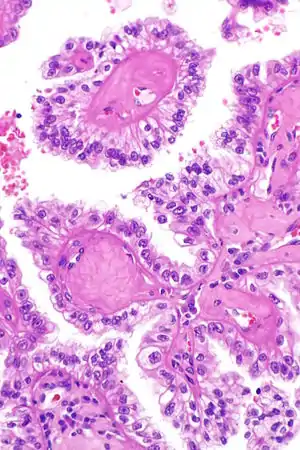

| Micrograph showing the characteristic hyalinized papillary cores found in some hereditary leiomyomatosis and renal cell carcinoma syndrome-associated renal cell carcinomas. H&E stain. | |

The renal cell carcinoma tends to be of the papillary (type 2) form and tends to occur more commonly in women than men with this syndrome. These cancers present earlier than is usual for renal cell carcinomas (typically in the twenties and thirties) and to be at relatively advanced stages at presentation. Tumours have rarely been reported in children. These tumours occur in ~20% of those with this mutation suggesting that other factors are involved in the pathogenesis.

The renal cell carcinomas have prominent eosinophilic nucleoli surrounded by a clear halo.